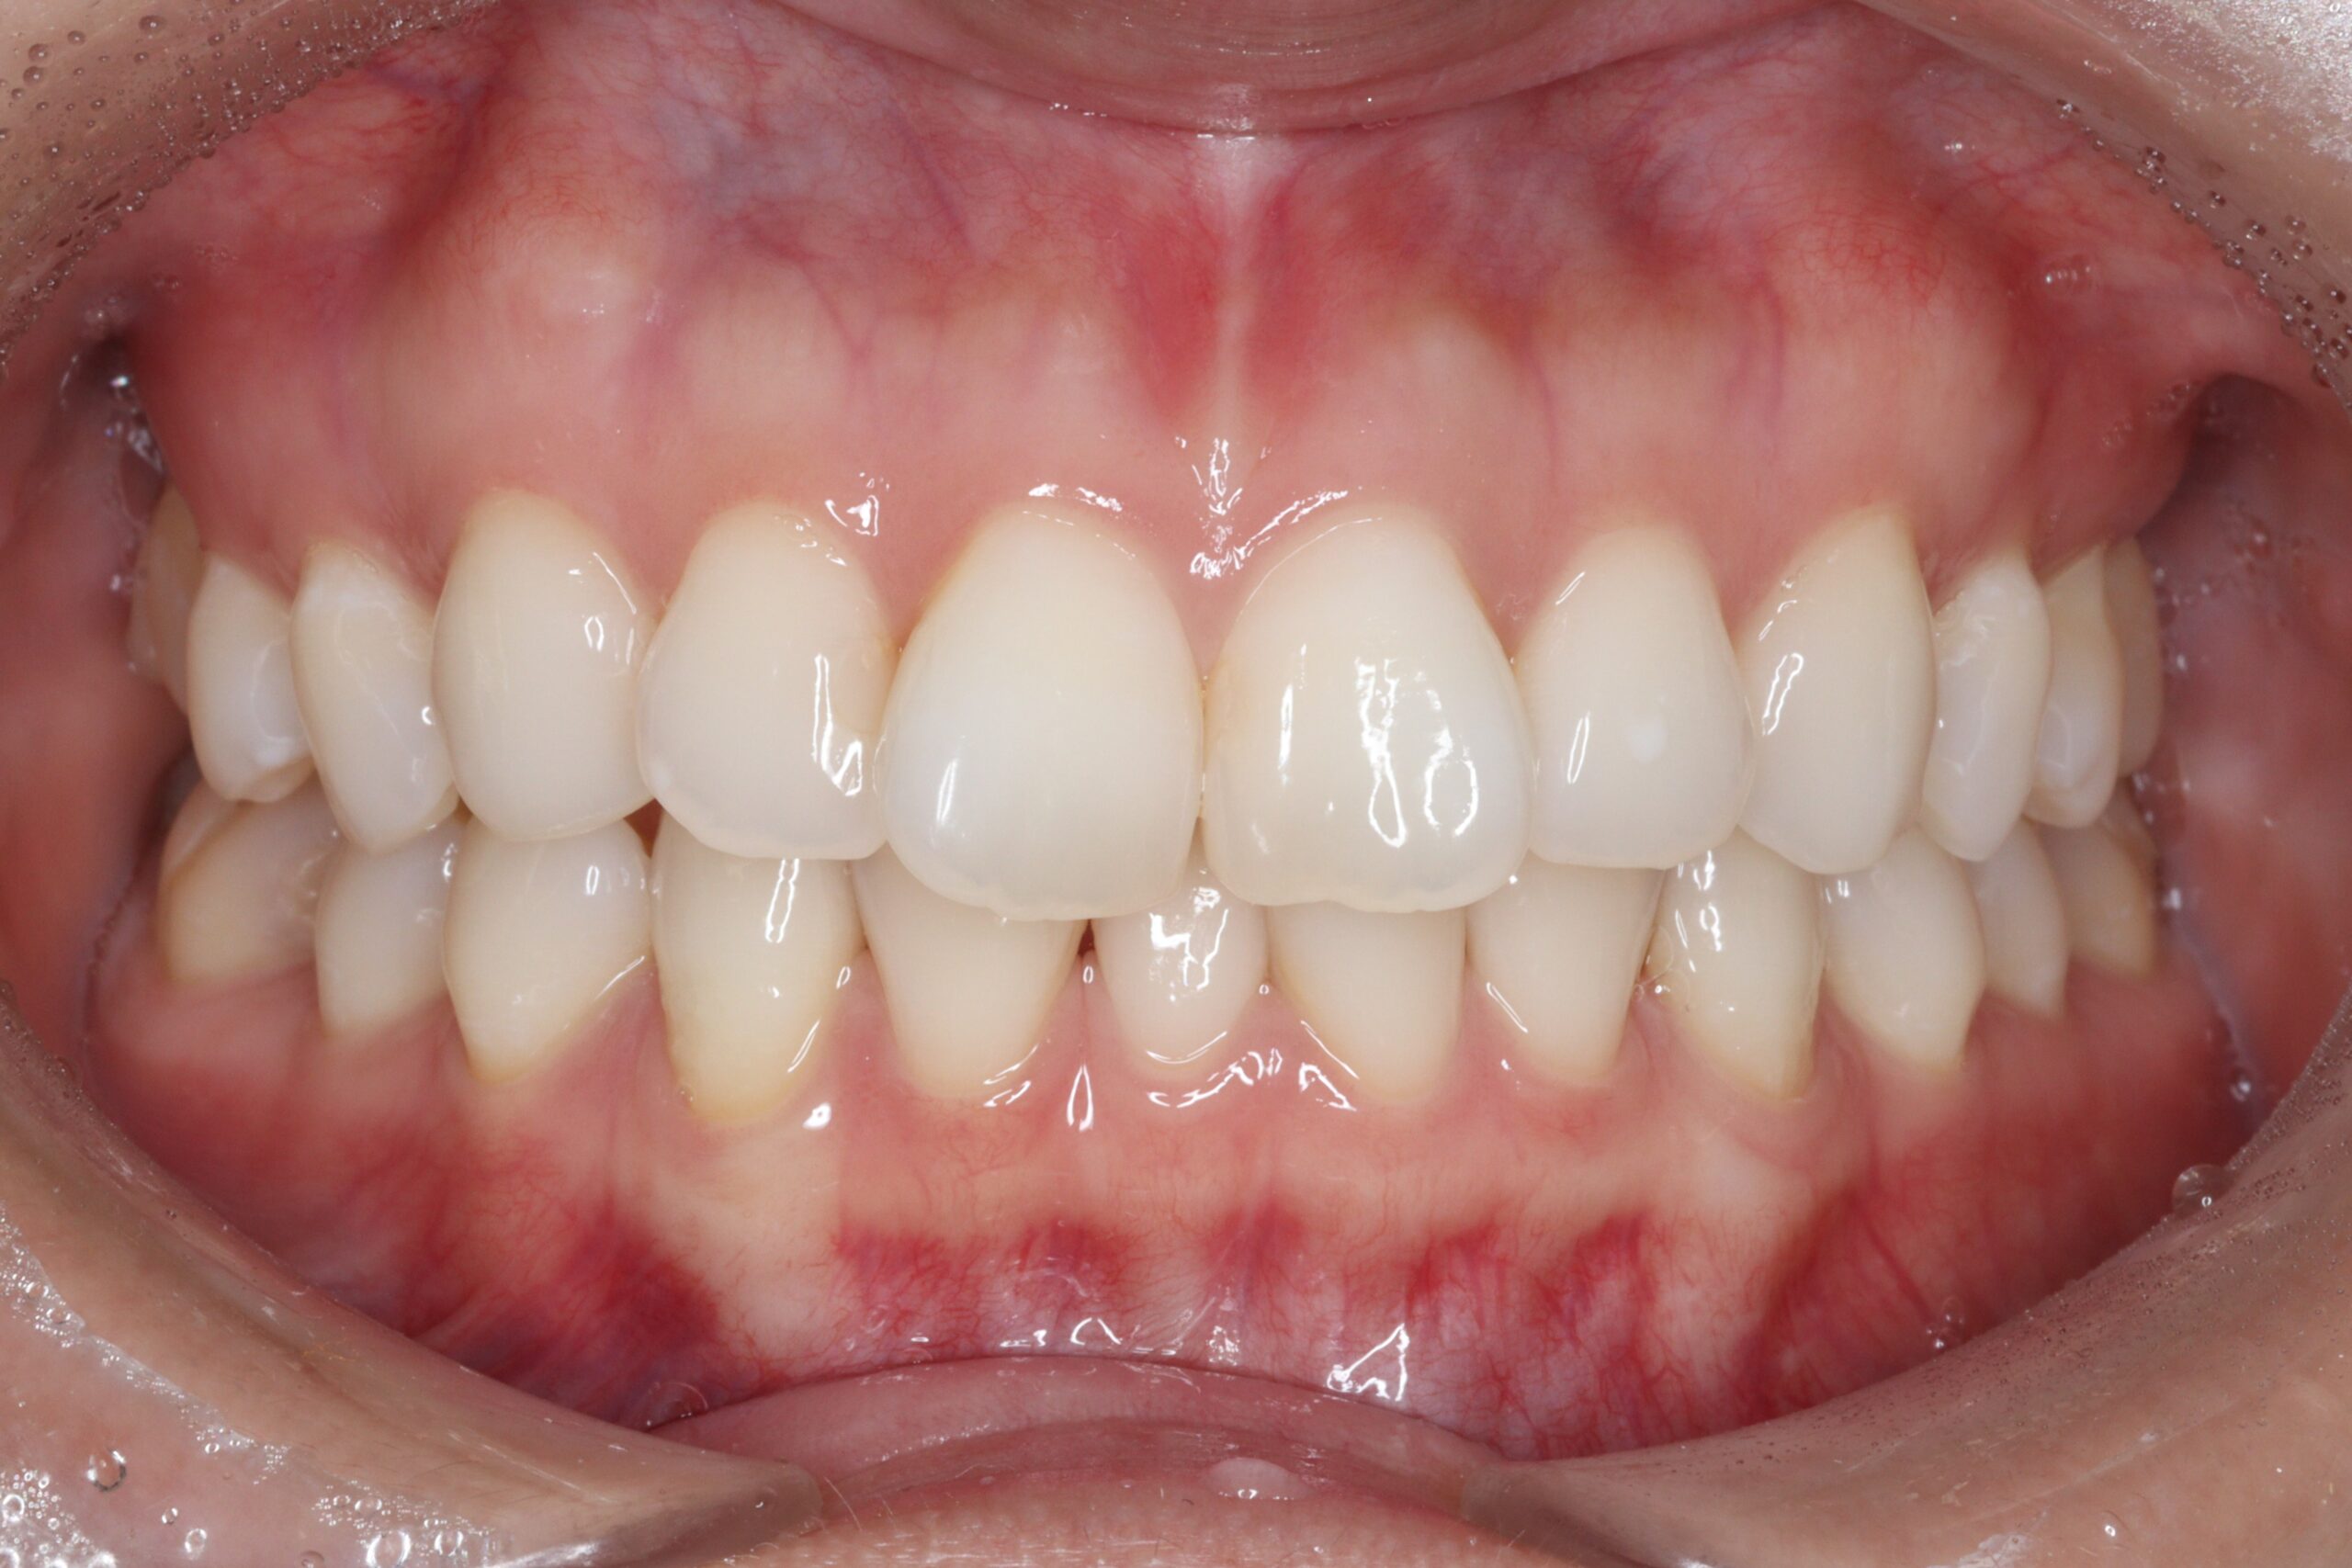

矯正術前:正面

矯正術後:正面